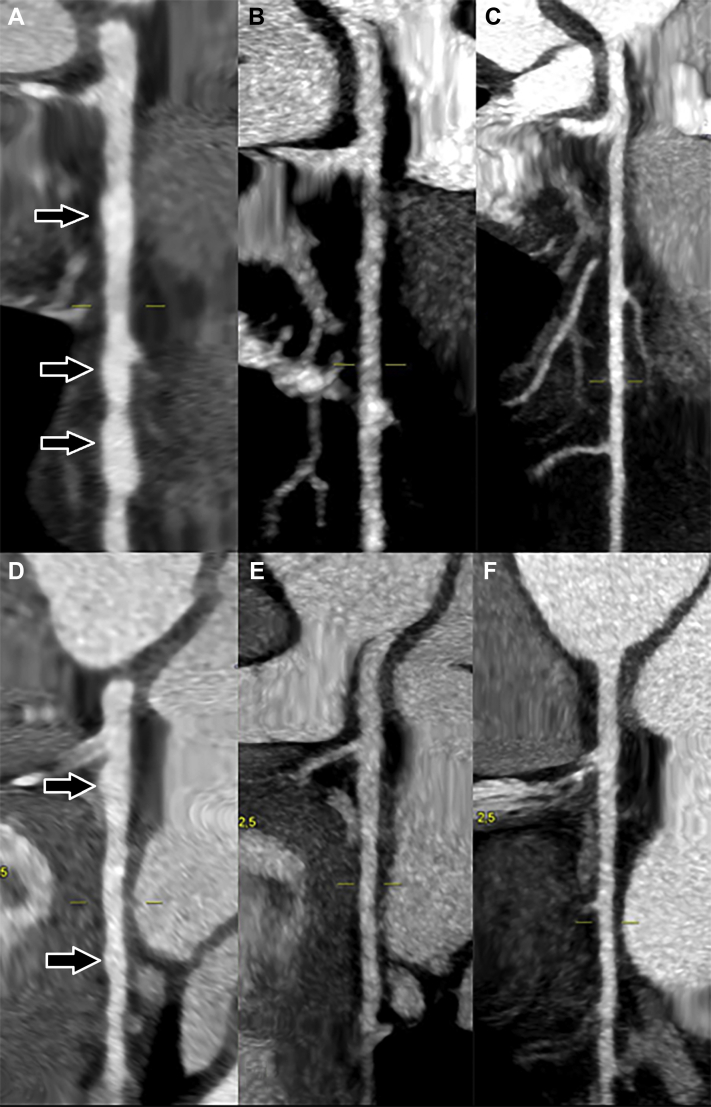

Figure 2.

Cardiac Computed Tomography Scans at 3 Different Time Points Showing Regression of the Aneurysms

Coronary computed tomography scan reconstruction at 3 different time points. Left anterior descending artery with multiple aneurysms (arrows) during the acute phase (A), with partial regression after 2 months (B) and total regression after 5 months (C). Circumflex artery with multiple aneurysms (arrows) during the acute phase (D), with partial regression after 2 months (E) and total regression after 5 months (F).

Two months later, while the patient felt fully recovered and his CRP level was <1 mg/L, a second coronary CT scan showed a partial regression of coronary aneurysms (Figures 2B and 2E). A TTE was repeated and confirmed the normalization of left ventricular function. Last, a third coronary CT scan performed 5 months after admission showed complete disappearance of all aneurysms (Figures 1B, 1D, 2C, and 2F).